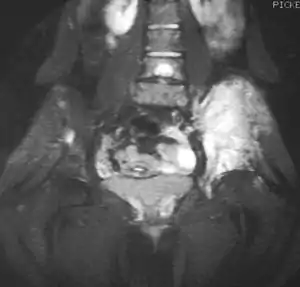

La resonancia magnética (IRM) podría ser usada rutinariamente en la investigación de los tumores malignos. La IRM mostrará la extensión total del tejido óseo y los tejidos blandos y establece la relación del tumor a las estructuras anatómicas cercanas (e.j. vasos sanguíneos).[14][15] Algunos investigadores sostienen que la IRM mejorada con contraste puede ayudar a determinar la cantidad de necrosis dentro del tumor, esto ayuda a determinar la respuesta al tratamiento antes de la cirugía.[15]

La TAC puede también ser usada para definir la extensión extraosea del tumor, especialmente en el cráneo, espina, costillas y pelvis. Tanto el TAC como la IRM pueden ser usados para el seguimiento al la respuesta del tumor a la radiación y/o quimioterapia.[14]